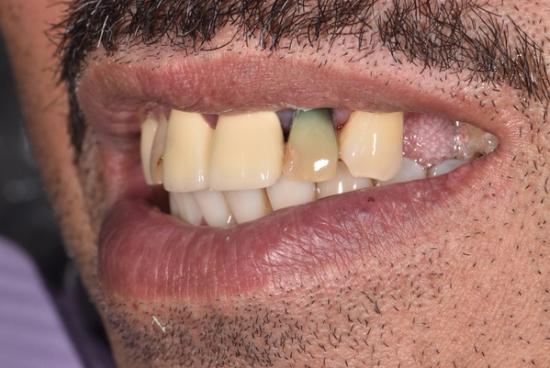

Before Photo